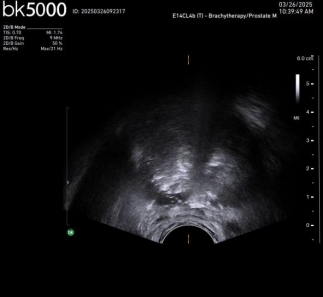

Case2. 超声定位电针穿刺及消融后改变